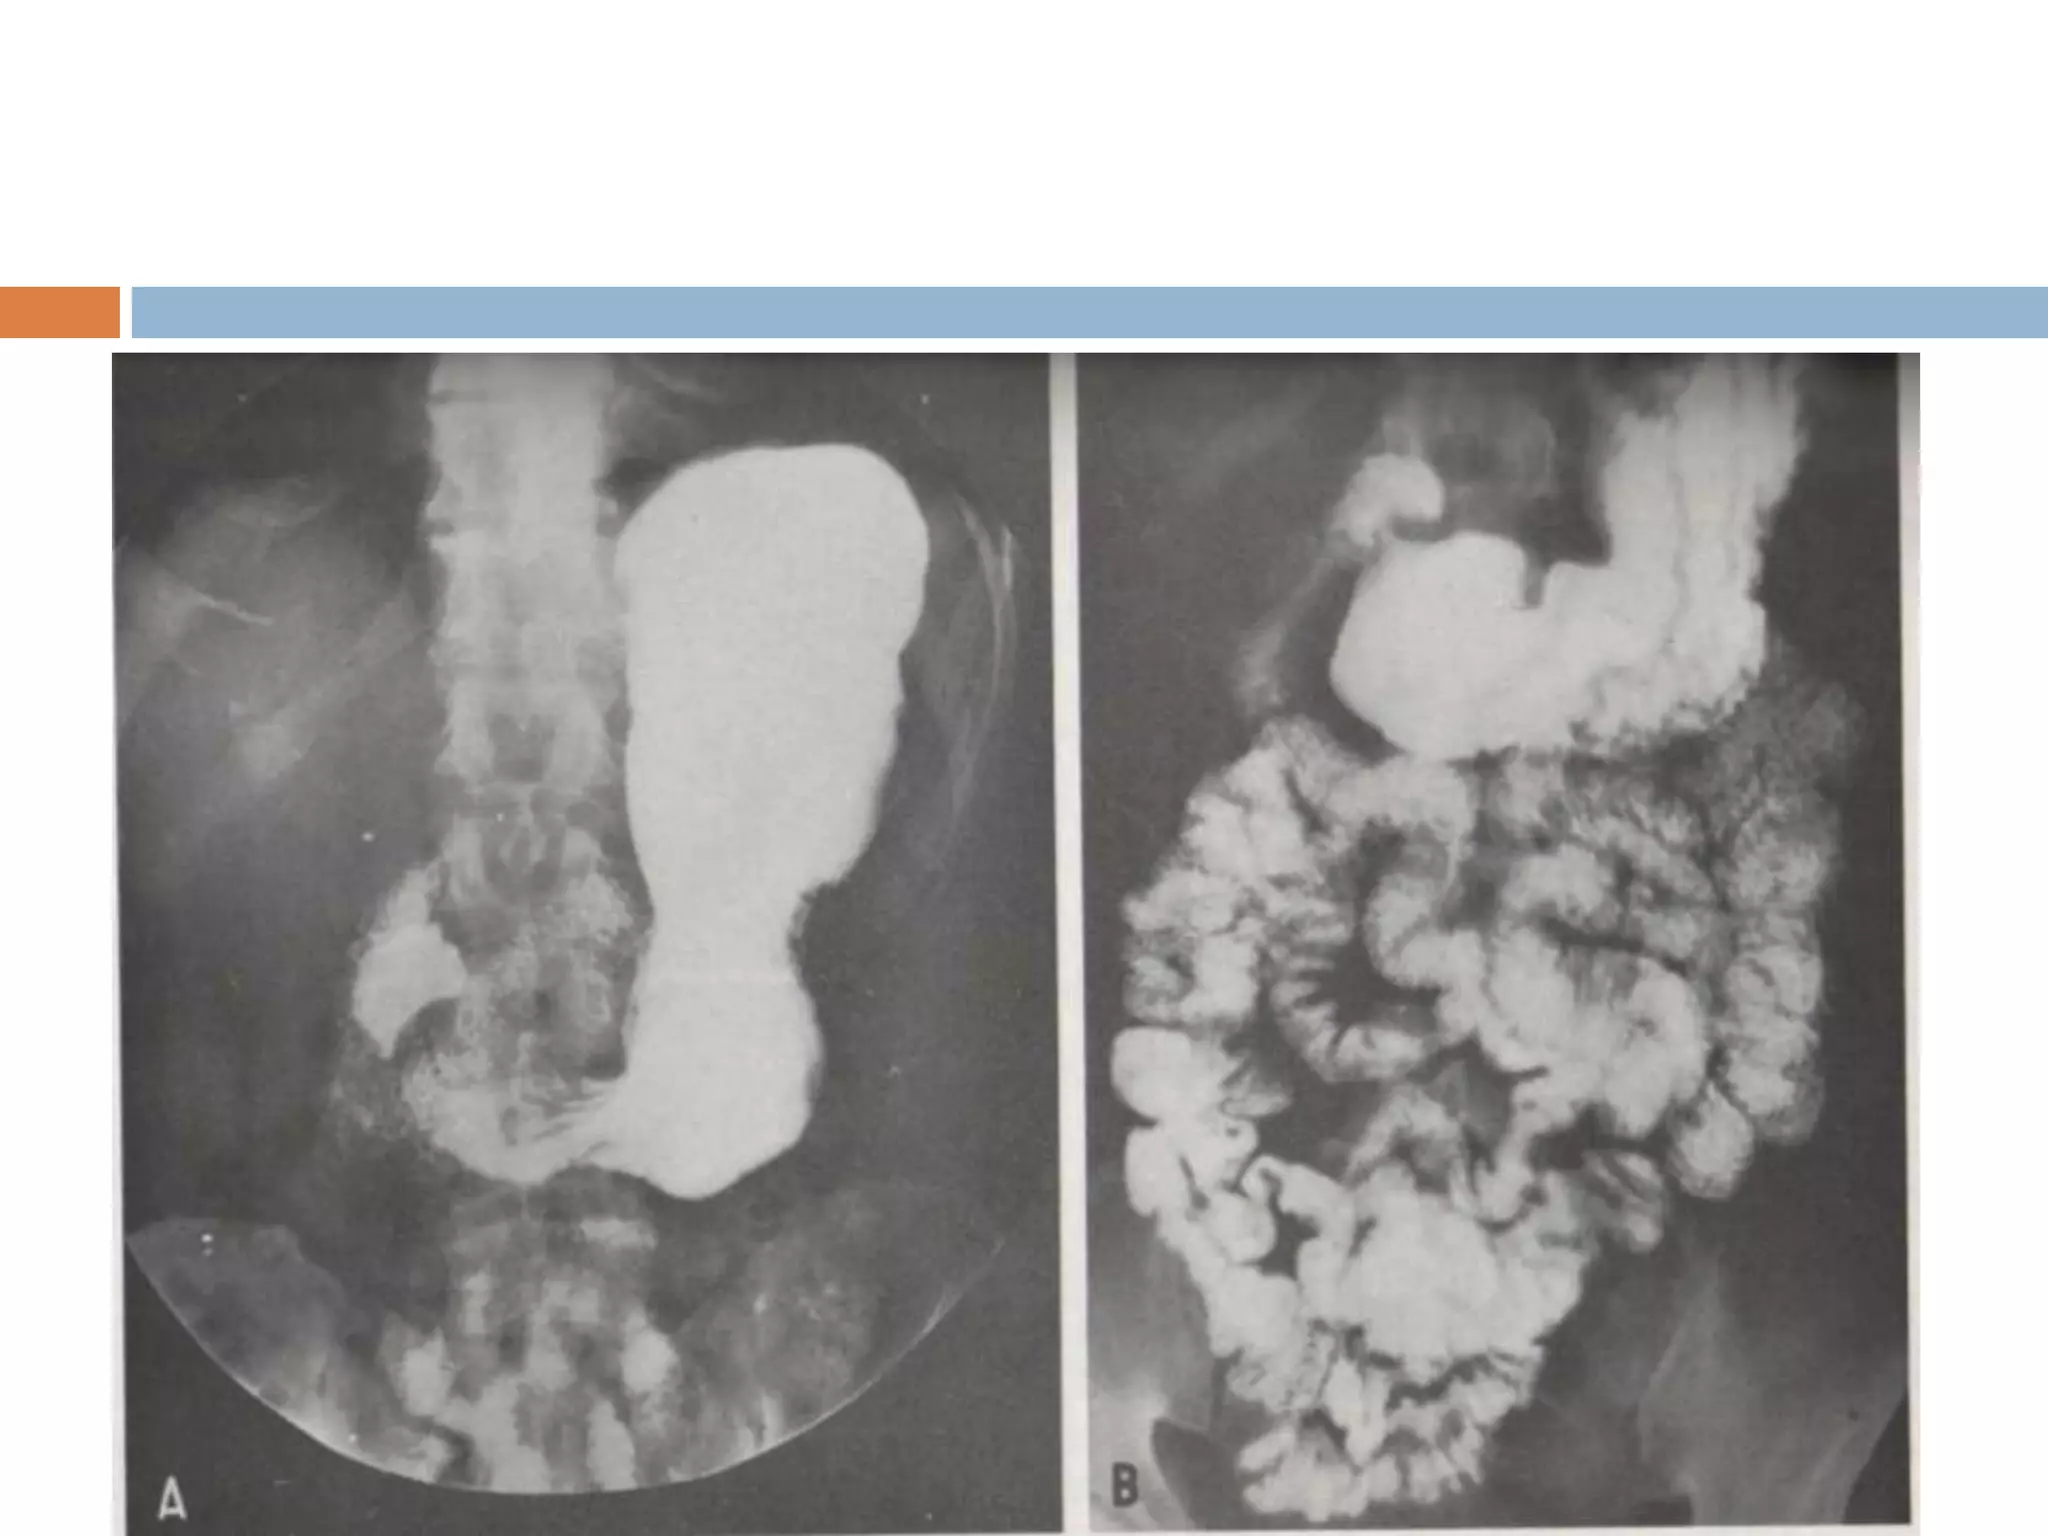

• El Fundus es la porción superior del estómago. Es

bipedestación (de pie). El signo radiológico se conoce

como cámara de gases.